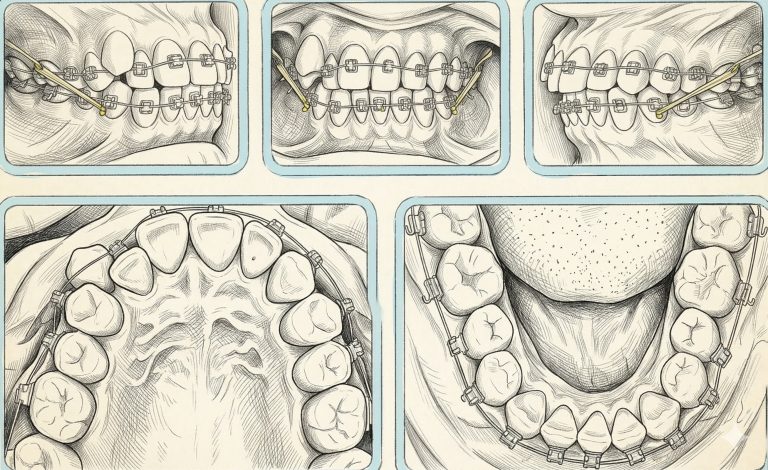

Para comenzar la semana traemos un artículo llamado Asymmetric mandibular arch distalization with third-molar … [Leer más...] acerca de Distalización asimétrica con extracción de terceros molares para la corrección no quirúrgica de la mordida abierta esqueletal clase III y desviación mandibular

Distalización asimétrica con extracción de terceros molares para la corrección no quirúrgica de la mordida abierta esqueletal clase III y desviación mandibular